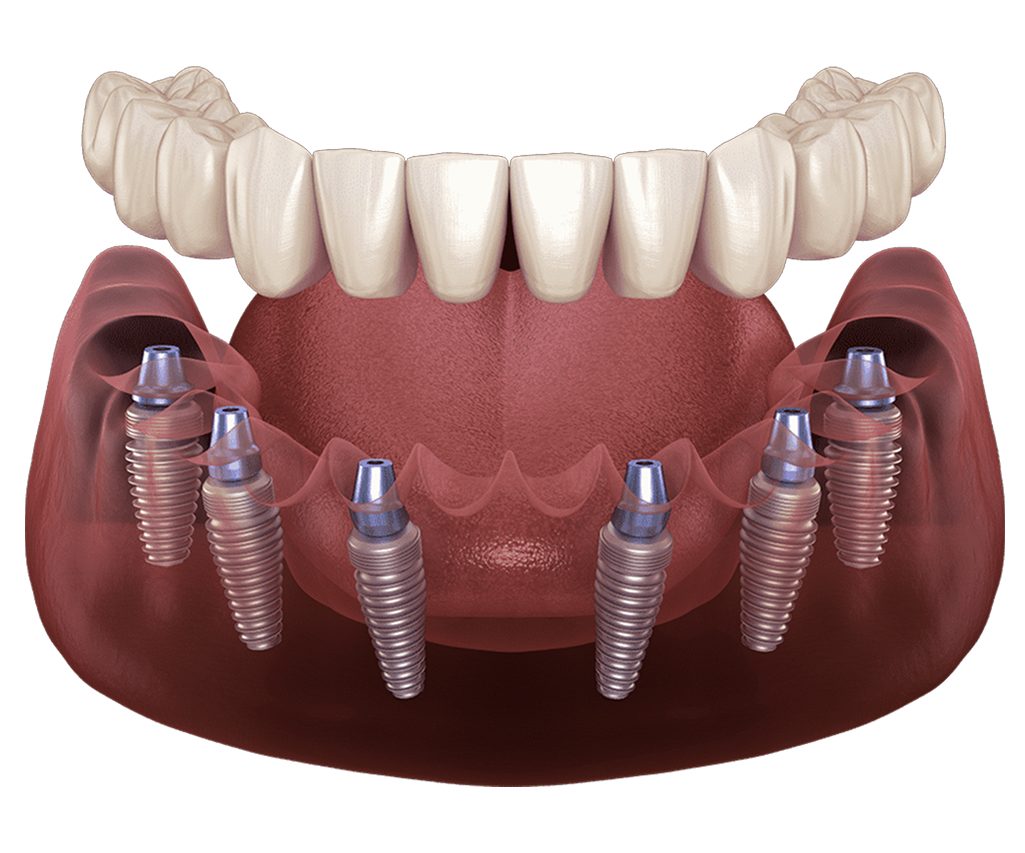

How to Determine the Most Accurate Price for All on Six Dental Implants

Achieving a precise financial roadmap for your all on six restoration

requires an understanding of the specific medical components involved.

Whether you are researching a single jaw or a full mouth restoration,

the first step is obtaining a clear unit price for the foundational

surgical phase.

Beyond the surgery, the structural system

used to fabricate your all on six prosthetic is a primary cost factor.

These advanced frameworks are classified into specialized categories

such as Titanium Bar, BioHPP Toronto, Titanium Toronto Hybrid, and CAD

CAM precision blocks. The second critical element is the selection of

the implant brand and its country of origin. Excluding professional

clinical fees, these two factors—the prosthetic type and the implant

brand—are the most significant variables determining your final

investment.